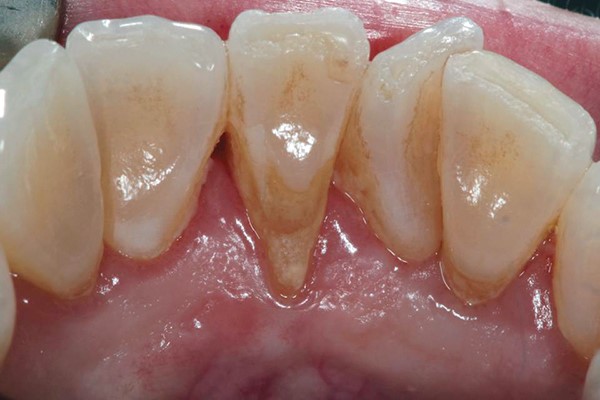

Tụt nướu (lợi) sẽ làm lộ chân răng bên dưới. Khu vực này thường không có men răng bảo vệ nên rất dễ bị vi khuẩn tấn công làm sâu răng.

(Tụt lợi làm lộ chân răng sẽ tạo điều kiện thuận lợi cho vi khuẩn tấn công và gây các bệnh lý)(**)